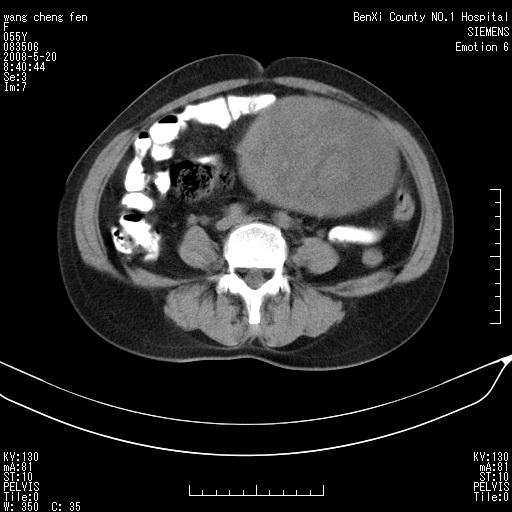

女、绝经后阴道流血3个月

左侧附件区可见一囊性占位,边缘清楚,内可见不规则形软组织影 ce:囊壁及内部可见强化 考虑 卵巢囊腺瘤

左侧附件区巨大囊实性病灶,边缘光整,病灶囊壁较厚,增强示囊壁及实性部分明显强化,强化呈度与宫体实质大致相同,宫腔积液征像,未见盆腔积液等其他异常,考虑左侧卵巢囊腺癌,不除外囊腺瘤及浆膜下肌瘤坏死

左侧附件区巨大囊实性病灶,边缘光整,病灶囊壁较厚,增强示囊壁及实性部分明显强化,强化呈度与宫体实质大致相同,宫腔积液征像,未见盆腔积液等其他异常。绝经后阴道流血3个月,结合病史左侧卵巢囊腺癌首先考虑,宫腔扩大不除外累及。期待结果。

支持浆膜下子宫肌瘤.之前由于网络原因未看全图片,现在重看,宫颈见一类圆形低密度影,增强轻度强化,低于肌层强化,宫腔扩大,考虑宫颈癌伴宫腔积液可能性大.

囊实性肿块分隔厚度较大,厚薄不均,增强实性成分明显强化,有不规则阴道流血,卵巢囊腺癌可能性大。

1,宫颈部占位,宫颈癌?2,左侧附件区囊实性占位,界较清,实质部分强化明显。考虑浆膜下或阔韧带肌瘤囊变可能大。囊腺类肿瘤不除外。